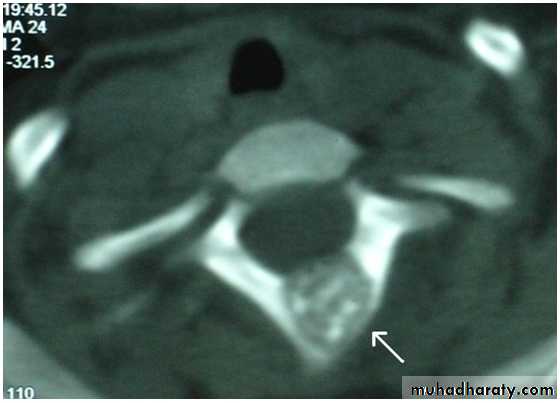

Osteoblastoma (giant osteoid osteoma)

It’s benign and similar to osteoid osteoma but its larger and more cellular.It occurs in young adults, males more than females.

Its commoner in the spine and flat bones& usually presents as pain or muscle spasm.X-ray shows well-defined lytic lesion surrounded by thin zone of sclerosis, it may contain flecks of calcification.

Treatment is by local excision and bone graft.

Always there is tendency for recurrence and malignant changes are reported.Bone cysts(tumor like conditions)